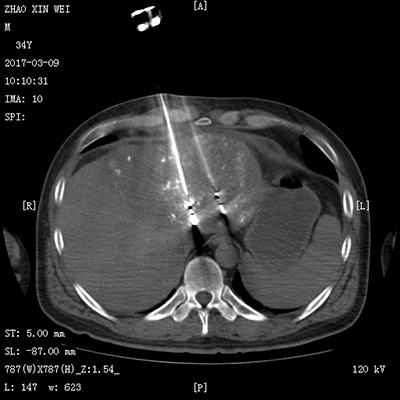

![]() | ![]() |

| (介入术中操作) | (肝癌的介入治疗) |